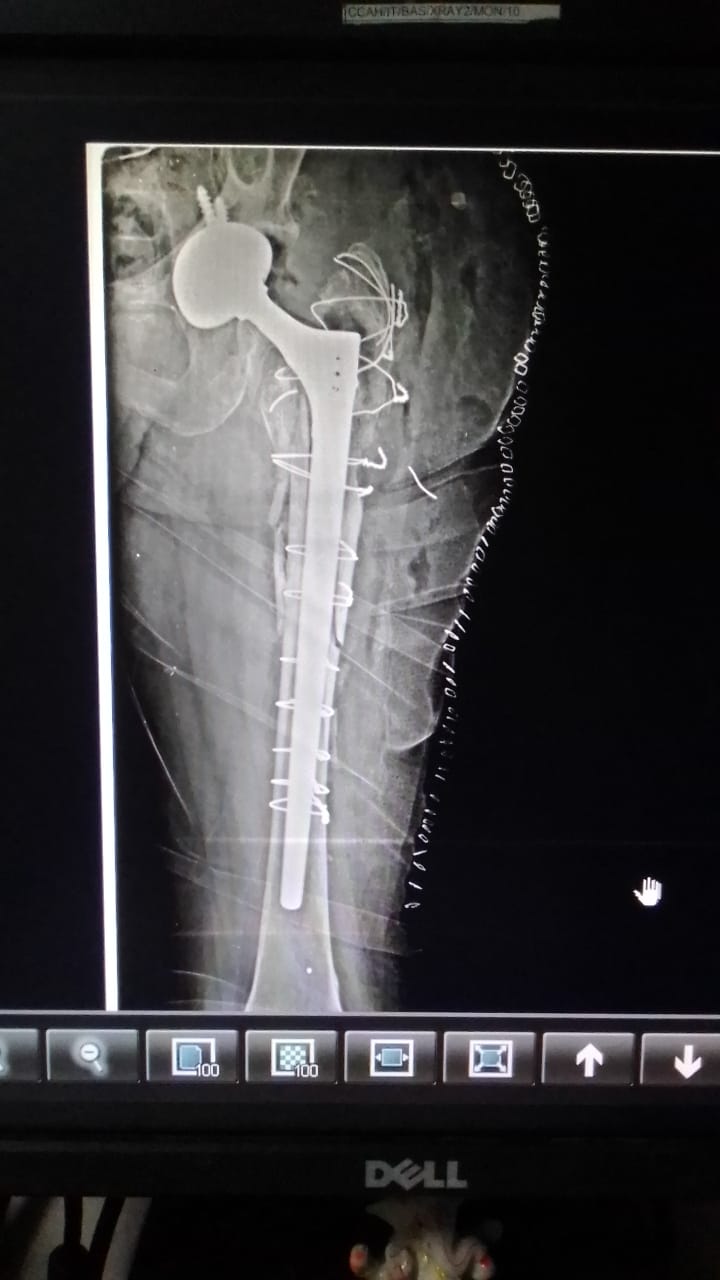

Dr Ajay Randive : IS MS Ortho (Mumbai) MRCSI ( UK) Consultant knee, Hip ,& Spine Surgeon, Dr Ajay Randhive is a eminent Knee, Hip , & Spine Surgeon practicing in to areas Andheri East,Santacruz East. Dr Ajay Randive did his MS Ortho residency from LTMMC, Sion Hospital Mumbai. He did overseas training in UK from 2003 till 2008. He is trained in total Knee Replacement, Hip Replacement, Revision Hip Replacement And Revision Knee Replacement Surgeries. He has worked at The Royal London Hospital. IN London where he worked a clinical fellow in joint Replacement unit. He has carried out more than 5000 Knee Replacement surgeries, 2500 Hip Replacement Surgeries, More Than 500 Revison Knee And Hip Replacement Surgeries 600 Spine surgeries & more than 1500 arthroscopic surgeries (Knee & Shoulder).